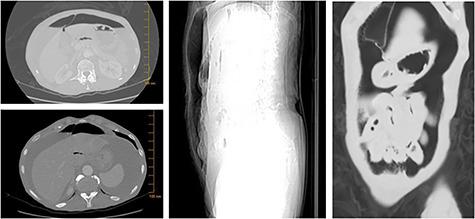

Primary signet ring cell carcinoma (SRCC) of the breast is extremely rare, and the associated patterns of metastatic dissemination poorly described. Here, we report the case of a 61-year-old woman presenting with acute abdominal pain. Esophagogastroduodenoscopy revealed a non-bleeding erosive gastropathy, which was biopsied and found significant for a poorly differentiated, GATA3-positive SRCC. The patient was lost to follow up until re-presenting 6 months later with a perforating duodenal ulcer and umbilical herniation. Biopsies of umbilical hernia sack contents were significant for an estrogen receptor (ER) positive SRCC, and breast examination identified a right breast mass significant for an ER positive lobular carcinoma with signet ring features, thereby affirming the diagnosis of metastatic SRCC of the breast. This case offers insight into an advanced form of a rare clinical entity, and suggests that staining for breast markers such as GATA3 should be considered for all biopsies significant for SRCC.

原发性乳腺印戒细胞癌(SRCC)极为罕见,其相关的转移播散模式鲜有描述。在此,我们报告一例61岁女性,因急性腹痛就诊。食管胃十二指肠镜检查发现一处无出血的糜烂性胃病,取组织活检后发现为低分化、GATA3阳性的SRCC。该患者失访,直到6个月后再次就诊,出现十二指肠溃疡穿孔和脐疝。脐疝囊内容物活检显示为雌激素受体(ER)阳性的SRCC,乳腺检查发现右乳有一肿块,为ER阳性、具有印戒特征的小叶癌,从而确诊为转移性乳腺SRCC。该病例为这种罕见临床实体的晚期形式提供了见解,并表明对于所有确诊为SRCC的活检组织,均应考虑检测乳腺标志物如GATA3。